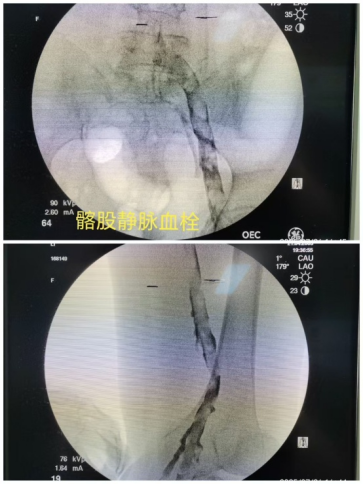

它就像是血管内部突然形成了“路障”,多发生于下肢。血液变得黏稠、流速减慢,或血管壁损伤时,就容易形成血栓。李阿姨的情况就属于典型突发血栓,并伴有血管严重狭窄,腿部肿胀明显、肤色变紫,医学上称为“股青肿”,需尽快处理。

第一步:放置“保护伞”(下腔静脉滤器),拦截可能脱落的血栓,同时用微导管吸出血栓,快速疏通血管;